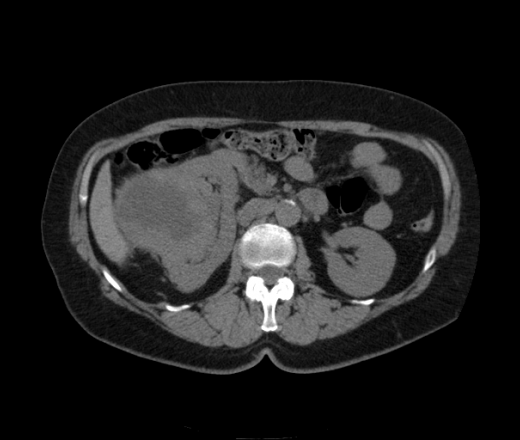

Солитарное кистовидное образование правой почки с неравномерно утолщенными стенками, у узлами в капсуле, накапливающими контраст. Фасция Гарота справа тяжистая. По классификации - киста 4-й категории, крайне велика возможность малигнезации. Может, показалось вовлечение парааортальных лимфоузлов?

Что за известковые включения на фоне патологически измененной почки?

В 1986 г. M.A. Bosniak создал “рабочую” классификацию кистовидных образований почек, которая позволяет предположить доброкачественность или злокачественность кистозных образований при распределении их по радиологическим критериям на 4 основные категории. Образования I и II категорий являются заведомо доброкачественными и поэтому нуждаются в динамическом наблюдении или, по показаниям, в лечебной пункции со склеротерапией под контролем УЗИ или КТ. Образования III категории могут быть как доброкачественными, так и злокачественными, а образования IV категории – кистозные почечноклеточные раки.

Третья категория – более сложные кистовидные образования, которые демонстрируют какие-либо радиологические признаки злокачественности. Некоторые из этих образований оказываются доброкачественными (например, сложные кисты, мультилокулярная кистозная нефрома, геморрагические кисты), другие злокачественными (почечные кистозно-клеточные карциномы). Одним из критериев, которые заставляютотнести кистовидное образование почки к III категории, является повышение плотности ее стенки. При КТ у кистовидного образования выявляется плотная (вплоть до обызвествления) стенка по всему периметру кисты, хотя образование может сохранять некоторые признаки простой кисты почки. Следующим критерием является характер отложения кальцинатов. Если при КТ в образовании определяется большое количество кальцинатов, расположенных глыбками (как на периферии образования, так и в центре), если из-за этого стенки и перегородки становятся утолщенными, неправильной формы, то данное образование следует отнести к III категории. Наличие множественных перегородок толщиной более 1 мм, видимых утолщений в месте прикрепления перегородок к стенкам кисты позволяет также отнести данное образование к третьей категории. Большое количество тонких перегородок в образовании определяет его как сложную кисту. Такие образования крайне сложно дифференцировать как доброкачественные или злокачественные, но они чаще по КТ-картине выглядят как злокачественные. При КТ определяется негомогенное многокамерное образование округлой или неправильной округлой формы, возможно с капсулой. Плотность образования неоднородная, пониженная относительно паренхимы, в полости образования видно большое количество перегородок.

IV категория – поражения явно злокачественные, обычно кистозные почечно-клеточные карциномы. Основными симптомами кистозной опухоли при КТ являются: неправильная форма кисты, негомогенность структуры образования с участками некроза, деформация почки, нечеткая граница между кистой и паренхимой почки, плотностные показатели могут быть выше, чем в кистах (+20…+40 Н), т.е. близкие к плотности почечной паренхимы. Капсула имеет неравномерную толщину, часто обызвествлена по периферии. Возможна визуализация дополнительных фокусов образования (кажущееся увеличение образования в размерах и изменение его конфигурации) после введения контрастного вещества. Но самым важным симптомом является увеличение плотности внутреннего содержимого после внутривенного введения контрастного вещества. Часто на серии срезов удается выявить эндофитные гребневидные фестончатые разрастания, выступающие в просвет кистозной полости. Особенно хорошо этот мягкотканый васкуляризированный компонент опухоли проявляется при внутривенном контрастировании

Всё верно, я тоже пользуюсь данной классификацией по Босняку, кистозно-солидное образование правой почки я отнёс к 4 категории, нужно отметить, что преобладает кистозный компонент, но солидный компонент довольно приличный и значительно накапливает контрастное вещество до 80-90HU, четко капсулу образования не отграничить. Ко всему этому в паренхиматозную фазу четко дифференцируются единичные парааортальные и паракавалльные л/узлы. С большей степенью вероятности в данном случае cr почки. Пациентка на следующей неделе будет госпитализирована для верификации.

Описание изменений, выявленных при микроскопическом исследовании: опухоль представлена крупными альвеолярными структурами из светлых, оптически пустых клеток с мелкими гиперхромными ядрами, опухоль частично инфильтрирует капсулу почки, полностью прорастает стенку почечной лоханки, образуя полиповидные структуры. Одиночные опухолевые эмболы в сосудах почки. Отдельно присланный узел представлен тканью почки с опухолевым узлом, строение которого соответствует выше описанной опухоли. В воротах почки патологических образований не найдено. Во всех исследованных лимфоузлах (6 шт.) метастазы опухоли с замещением всей ткани лимфоузлов.

Патоморфологическое заключение: массивный светлоклеточный почечно-клеточный рак почки с частичной инфильтрацией капсулы, прорастанием в ЧЛС, опухолевыми эмболами в сосудах, множественными метастазами в забрюшинные лимфоузлы (6 шт